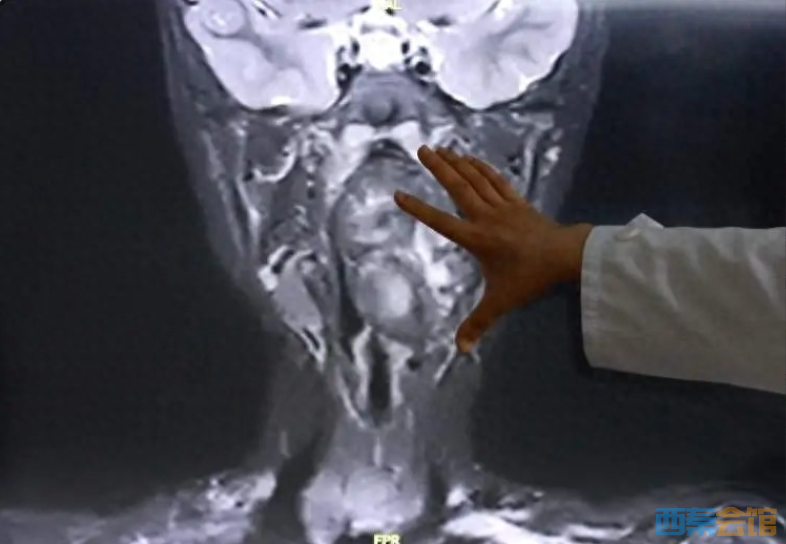

近日,小亮来到复旦大学附属儿科医院就诊,经增强CT及磁共振检查,明确小亮所患的肿瘤约7×3.5×3cm,犹如“拳头”般大小。专家表示,该肿瘤紧邻颈内动静脉并将血管明显向外推移,肿瘤向咽喉腔内隆起,占据大部分口咽及下咽腔,严重压迫声门,随时可能发生窒息。 鉴于病情危重、解剖结构复杂,儿科医院耳鼻咽喉头颈外科立即联合麻醉科、重症医学科的专家开展多学科评估与术前讨论,制定经口微创、精准安全的个体化手术方案。因手术风险极高,为了避免术中可能发生的意外情况,救治团队同时制定了详尽的备选手术方案。